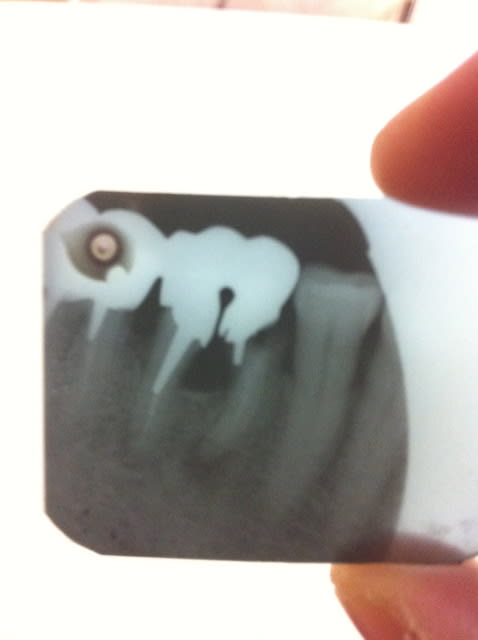

Examen clinique, effectivement mobilité terminale des incisives, il faut les extraire. Je lui explique, il est d'accord. Je lui dit que je ne peux pas lui faire un provisoire immédiat mais un simple provisoire car si je prends l'empreinte avec les dents, tout va rester dans le porte empreinte. Pour voir sur quoi je peux m'appuyer, je fais des radios des couronnes postérieures. Secteur 3, le bridge est ok. Secteur 4, c'est là que la merde commence.

La 46 est foutue (à mon humble avis): infection apicale, atteinte furcatoire, faux-moignon guère mieux.

La 47 présente une perte d'attache quasi jusqu'à l'apex en distal.

Ps: désolé pour les photos, radio argentique oblige.

Celle-ci elle a surtout de la merde dans les yeux (quand tu vois l'état de la 46!!!)

Je trouve ça quand même dingue que la DC me donne tord vu l'état des molaires.